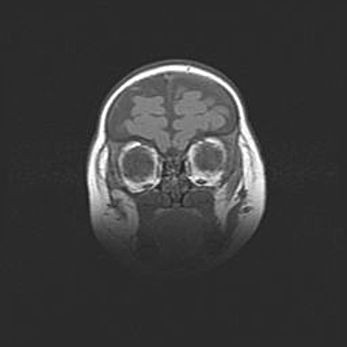

Неполная лизэнцефалия (пахигирия). Открытая гидроцефалия.

Возраст: 17 дней

Вес: 3110 г

Пол: мужской

Окружность головы: 33,5 см

Срок гестации: 35-36 недель

Лизэнцефалия—недоразвитие корковой пластинки и мозговых извилин в результате нарушения миграции нейронов коры. Поверхность мозговых полушарий гладкая. Микроскопически выявляется отсутствие нормальных слоев коры и скопление групп нейронов в подкорковом белом веществе.

Пахигирия—уменьшение числа вторичных извилин. В пораженном полушарии нервные клетки образуют толстый недифференцированный слой с неправильно расположенными нервными волокнами и группами гетеротопных клеток. Нервные клетки незрелые. Белое вещество истончено. При этом нередко аномально развит корково-спинномозговой путь.